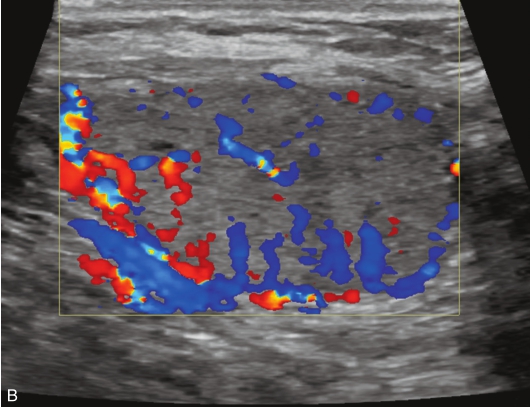

女性,65岁,发现“右侧颈部肿块2年余”就诊,其他无特殊。

甲状腺腺瘤伴囊性变常规超声图像,见图1-3-22。

图1-3-22 甲状腺腺瘤伴囊性变常规超声示意图

A.灰阶图像示甲状腺右叶内可见以囊为主的混合回声,边缘光滑,纵横比<1,实性部分呈等回声,回声均匀;B.CDFI血流成像示结节内部及边缘可见丰富血流信号

甲状腺腺瘤伴囊性变超声造影图像,见图1-3-23、ER1-3-11。

甲状腺腺瘤伴囊性变超声造影表现为病变内实性部分与周围正常甲状腺组织同步或稍早于周围甲状腺组织,呈弥漫性均匀性等增强或稍高增强,与周围正常甲状腺组织同步消退。病灶囊性部分呈无增强。病灶边缘可见环状高增强。

实性部分超声造影多表现为呈均匀或不均匀等增强,结节边缘无环状高增强。

实性部分超声造影达峰时多表现为不均匀低增强。

图1-3-23 甲状腺腺瘤伴囊性变超声造影图

A.增强早期;B.达峰时;C.增强晚期

ER1-3-11 甲状腺腺瘤伴囊性变超声造影视频

视频注解:在造影剂注射后10s病灶实质部分与甲状腺实质同步增强、同步廓清呈等增强,囊性部分呈无增强,结节周边可见环状高增强